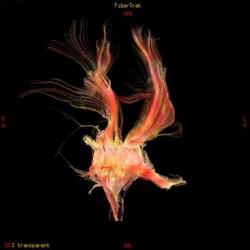

Асимметрия трактов головного мозга в результате их смещения:

А что дают в данном случае ангиография и тем более трактография? Потеря времени ведь только, а ведь с такой патологией может быть дорога каждая минута...

И по-прежнему для меня остается загадкой, какую дополнительную информацию можно получить здесь при МР-трактографии.

Работая совместно с нейрохирургами, которые занимаются сосудистой патологией, перед нами постоянно ставят именно эту задачу: определить причину кровоизлияния, а отсюда и тактику доступа при нейрохирургическом вмешательстве (пункционно идти на ту или иную гематому или открытым доступом или вообще не вмешиваться и вести определенных больных консервативно). Вы правы, что при таком обширном кровоизлиянии МР-ангиография (особенно на 2-3 сутки после начала заболевания) часто оказывается бесполезной, так как из-за зоны кровоизлияния определенная часть сосудов основания мозга просто не визуализируется, или значительно смещена и деформирована именно зона интереса, что увеличивает риск неправильной трактовки данной патологии. Тогда нейрохирургам приходится применять классическую селективную ангиографию (если они действительно подозревают аневризму). Но в данном случае мы видим МР-томограммы и МР-ангиограммы в первые часы гемор.инсульта, поэтому сосуды хорошо получились. А МР-трактография (у нас нет такого оборудования как у Евгения, поэтому мы эту методику не применяем) может тоже помочь планировать операционный доступ и объем оперативного удаления гематомы с учетом видения расположения проводящих путей, их заинтересованности в патологическом процессе с целью минимальных послеоперационных осложнений и неврологического дефицита. Эта методика сейчас актуальна не только для изучения опухолей но и сосудистых заболеваний. С уважением Visus 07

В общем и целом я абсолютно согласен. Прямое показание к трактографии - это планирование операционного доступа.